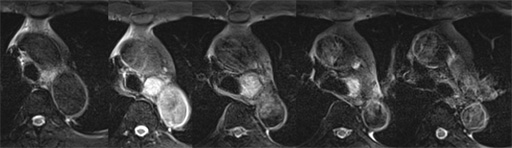

図6 胸部CT 肺野条件 図7 MRI T1WI (in phase)

図7 MRI T1WI (in phase) 図8 MRI T1WI (out of phase)

図8 MRI T1WI (out of phase) 図9 MRI T2WI

図9 MRI T2WI 図10 MRI fat sat T2WI

図10 MRI fat sat T2WI 図11 MRI fat sat T1WI

図11 MRI fat sat T1WI